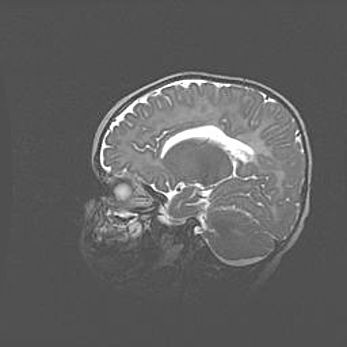

Мальформация Денди-Уокера. Киста задней черепной ямки.

Агенезия мозолистого тела.

Возраст: 2,5 месяца

Вес: 2420 г

Пол: женский

Окружность головы: 37 см

Срок гестации: 32 недели

Мальформация Денди—Уокера — редкий вид патологии ЦНС, представляющий собой врожденный порок развития каудального отдела ствола и червя мозжечка, ведущий к неполному раскрытию срединной (Мажанди) и латеральных (Лушка) апертур IV желудочка мозга. Для этогно синдрома характерна триада симптомов: гипотрофия червя мозжечка и/или полушарий мозжечка, кисты задней черепной ямки, гидроцефалия различной степени. В 70% случаев порок сочетается и с другими аномалиями головного мозга, в частности с агенезией мозолистого тела.